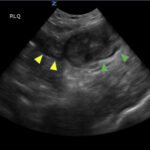

Small bowel diverticulitis is an uncommon subset of acute diverticulitis and can mimic many other intra-abdominal processes. As a result, imaging modalities such as ultrasound and computed tomography (CT) scan are especially important for timely recognition of diverticulitis and can expedite diagnosis and treatment and reduce complications. In the case described in this report, an 81-year-old male with history of esophageal cancer and recurrent diverticulitis with history of multiple bowel resections presented to the emergency department (ED) with right lower quadrant abdominal pain and constipation. Findings on ultrasound were suggestive of diverticulitis, and findings on CT of the abdomen and pelvis showed ileitis with phlegmon and micro-abscess suspicious for small bowel diverticulitis. ED providers should familiarize themselves with ultrasound findings of diverticulitis and be aware that diverticulitis can also present in the small bowel. Treatment of small bowel diverticulitis is similar to colonic diverticulitis.